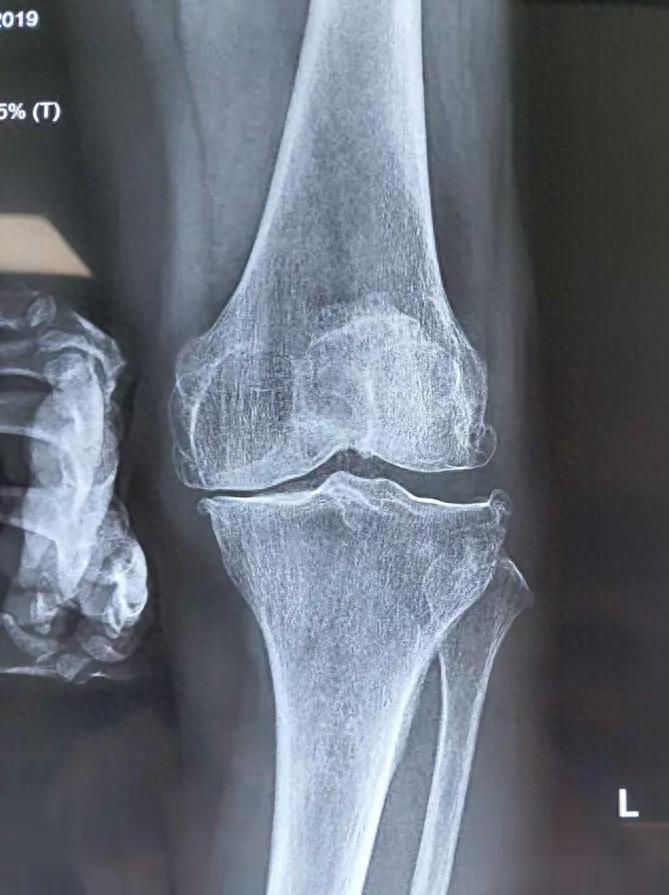

一、 真实病例:从“置换名单”到重登讲台开头提到的那位教师,姓王。进来时左膝严重内翻,软骨磨损达到IV级(最重级),片子上几乎看不到关节间隙。